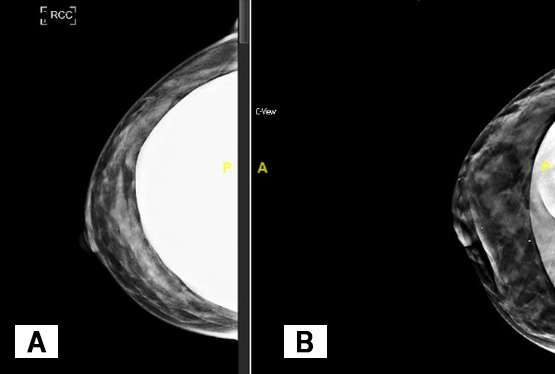

Breast implants appear dense on mammographic images and can obscure normal breast tissue. For patients with breast augmentation, the Mammographic Quality Standards Act recommends two additional views of each breast in addition to the standard views described in the aforementioned text.2 While the standard MLO and CC views are obtained with the implant included and with lighter compression to prevent implant rupture, the additional “implant displaced” views are performed under normal compression with as much of the implant excluded from the image as possible (Figure 3). A closer evaluation of normal breast parenchyma can be assessed on the implant displaced views while the implant included views allow for visualization of both the implant and a general overview of the breast.